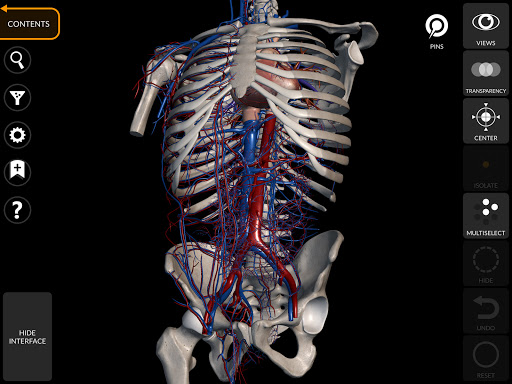

يتيح لك "Anatomy 3D Atlas" دراسة التشريح البشري بطريقة سهلة وتفاعلية.

من خلال واجهة بسيطة وبديهية، من الممكن ملاحظة كل بنية تشريحية من أي زاوية.

تتميز النماذج التشريحية ثلاثية الأبعاد بتفاصيل خاصة ودقة تصل إلى 4K.

يسهل التقسيم حسب المناطق والمناظر المحددة مسبقًا مراقبة ودراسة الأجزاء الفردية أو مجموعات الأنظمة والعلاقات بين الأعضاء المختلفة.

نماذج تشريحية ثلاثية الأبعاد

• الجهاز العضلي الهيكلي

• الجهاز القلبي الوعائي

• تدوير وتكبير كل نموذج في مساحة ثلاثية الأبعاد

• خيار إخفاء أو عزل نموذج واحد أو نماذج متعددة مختارة

• فلترة لإخفاء أو عرض كل نظام

• وظيفة الشفافية